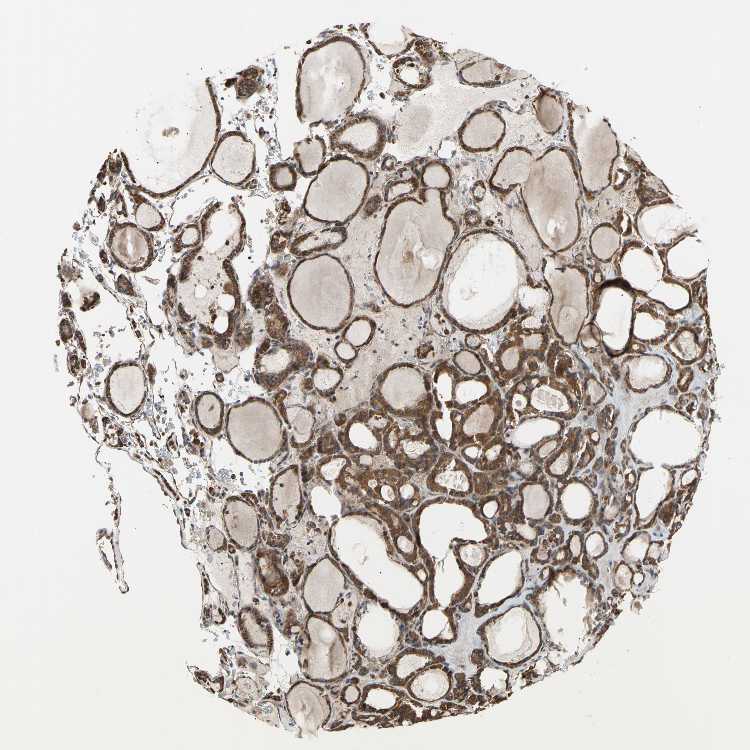

TISSUE PRIMARY DATA THYROID GLAND Show tissue menu

THYROID GLAND - Antibody stainingi

Antibody staining in the annotated cell types in the current human tissue is reported as not detected, low, medium, or high, based on conventional immunohistochemistry profiling in selected tissues. This score is based on the combination of the staining intensity and fraction of stained cells.

Each image is clickable and will lead to virtual microscopy that enables deeper exploration of all samples and also displays staining intensity scores, fraction scores and subcellular localization as well as patient and tissue information for each sample.

Antibody HPA020095Antibody HPA020138Antibody CAB010878Antibody CAB080402

Glandular cells MediumMediumMediumMedium